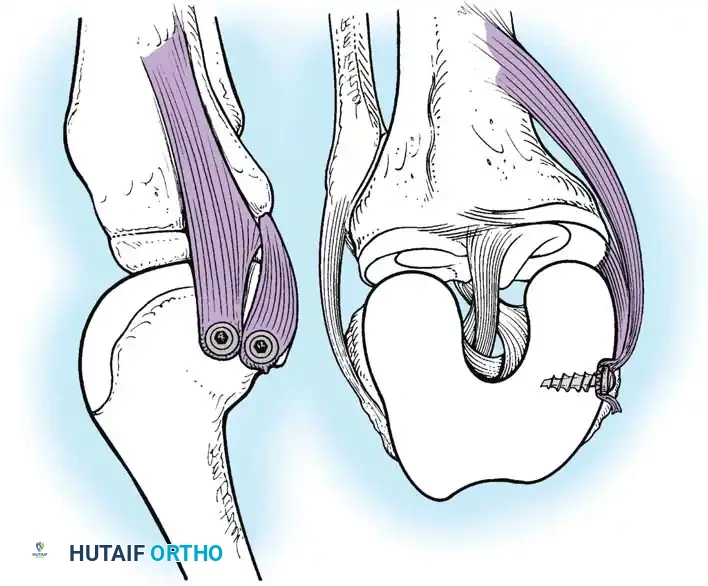

Lateral Collateral and Posterolateral Corner (PLC) Repair

Lateral-sided injuries are notoriously unforgiving and rarely heal with conservative management due to the inherent varus alignment of the lower extremity during the normal gait cycle.

A curvilinear incision is made over the lateral aspect of the knee, incorporating the iliotibial band and the biceps femoris. The common peroneal nerve must be identified, neurolysed, and protected with a vessel loop throughout the procedure.

Image

The LCL, popliteus tendon, and popliteofibular ligament are systematically evaluated. Avulsions from the fibular head are common.

Deep capsular tears are repaired with interrupted sutures. If the LCL or popliteus is avulsed from the lateral femoral epicondyle, anatomical footprints are identified, and the structures are repaired using suture anchors. Tensioning must be performed with the knee in 30 degrees of flexion and neutral rotation.

In cases where the native tissue is non-viable or the injury is subacute, an anatomical posterolateral corner reconstruction using an autograft or allograft (e.g., Achilles or semitendinosus) is mandated. The graft is routed to recreate the LCL and popliteofibular ligament.

Robust fixation is achieved using interference screws or screw-and-washer constructs in the fibular head and lateral femoral condyle. The biomechanical integrity of the construct is verified by taking the knee through a full range of motion, ensuring no impingement or laxity.